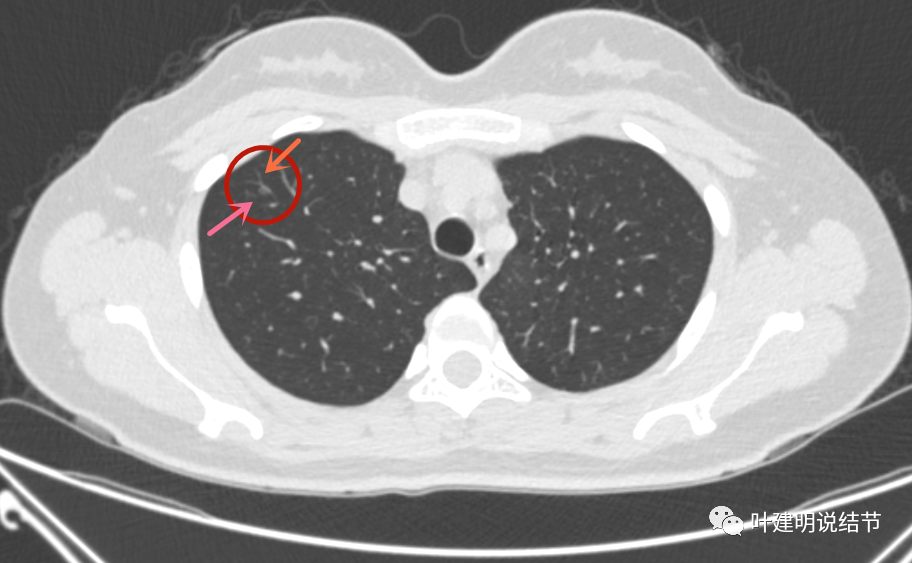

有空泡征的磨玻璃结节多提示恶性可能性大,建议尽早外科干预.